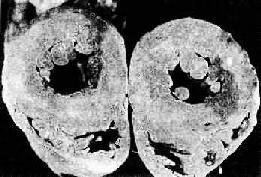

4.腎臟 在低血流量灌注時,各重要器官中,最早受影響的是腎臟。因老年人最容易腎動脈硬化、腎小管萎縮。所以當腎血流量減少到一定程度時,腎臟微循環內微聚物形成,腎小管上皮壞死,發生腎功能衰竭。臨床表現為少尿或無尿,尿素氮(BUN)>35.7mmol/L(100mg/dl),肌酐(Cr)176μmol/L(2mg/dl)。